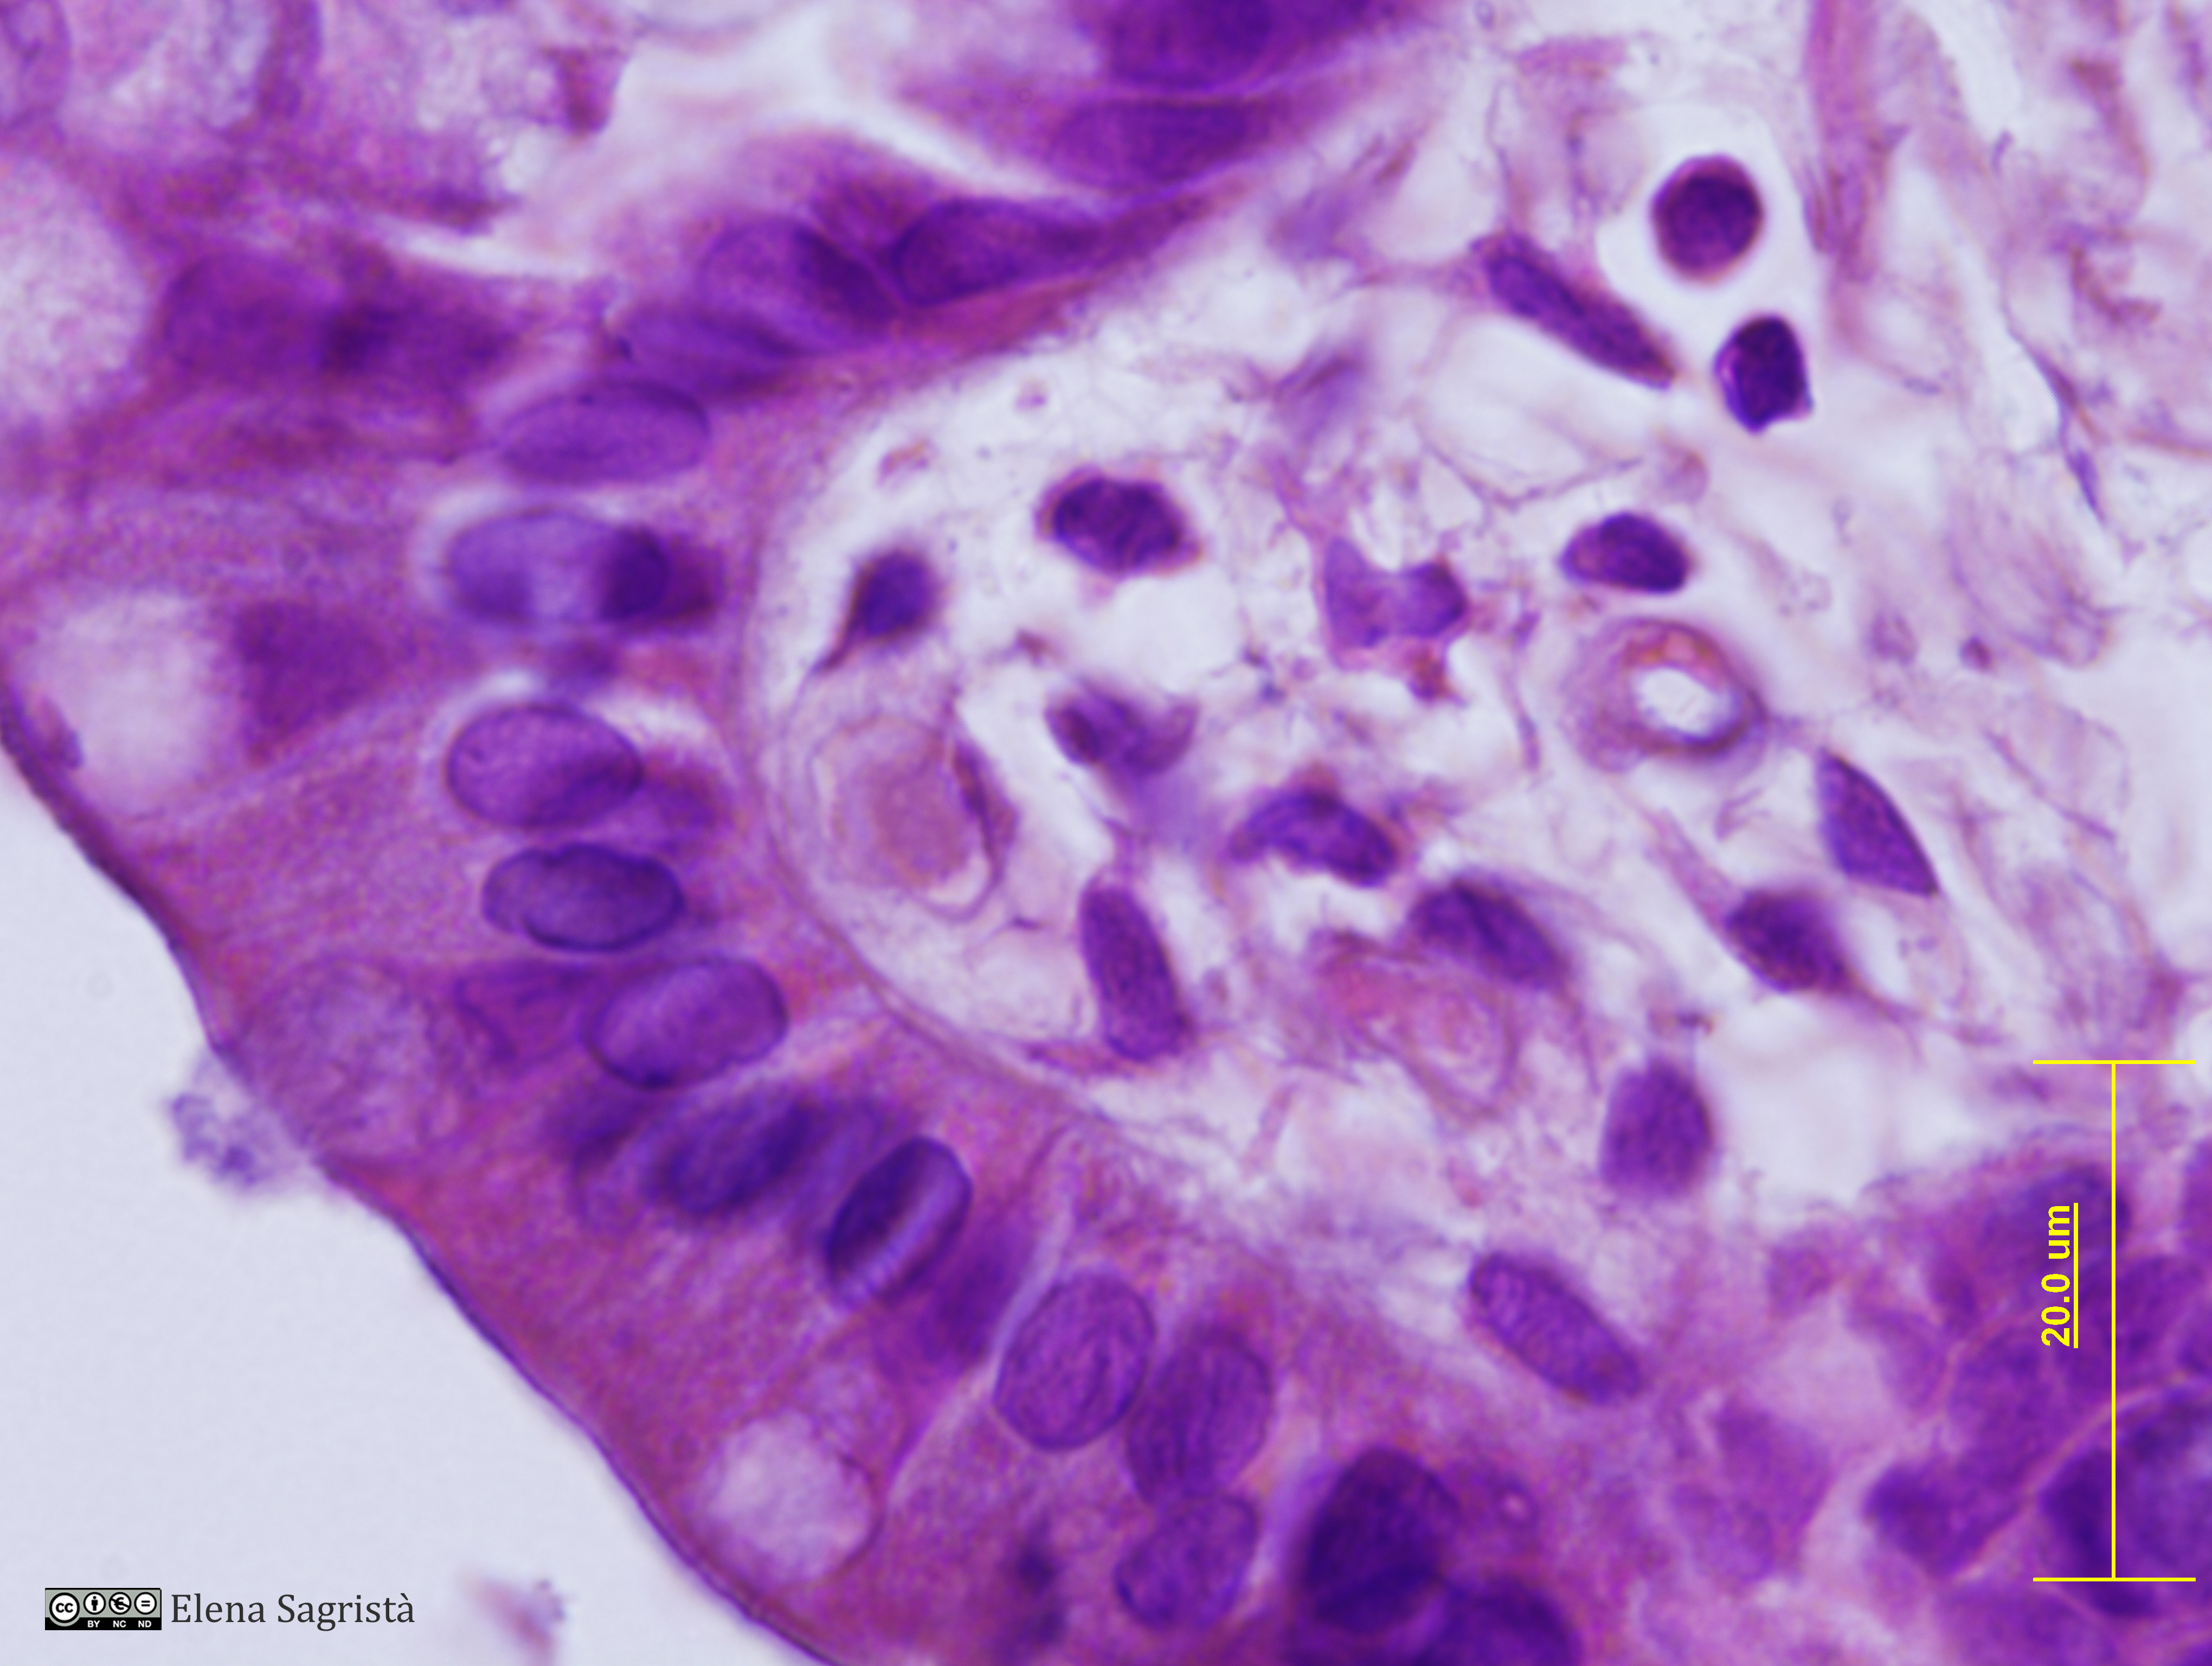

Imatges de preparacions histològiques de teixit epitelial. Microscopia òptica.